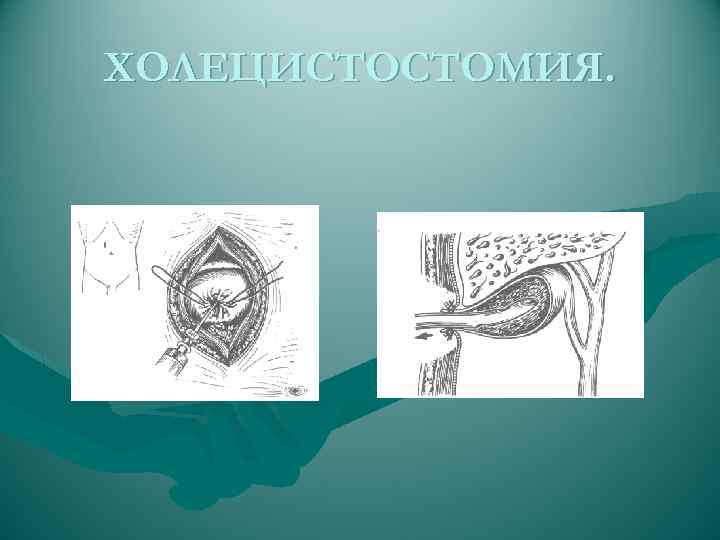

ХОЛЕЦИСТОСТОМИЯ.

ХОЛЕЦИСТОСТОМИЯ.

ХОЛЕЦИСТОСТОМИЯ.

ХОЛЕЦИСТОСТОМИЯ.